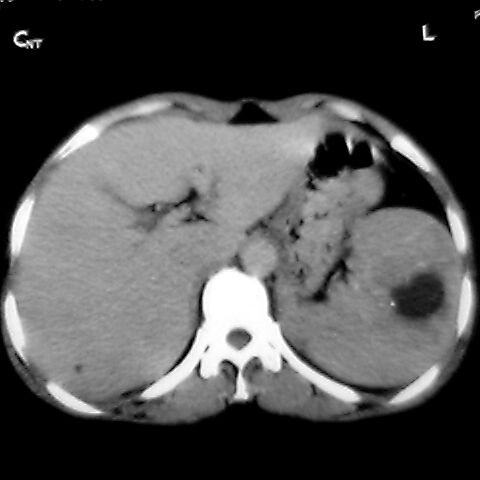

标题: [原创]CT4167脾占位。请大家帮忙会诊。

女 48岁 食道癌术前体检发现脾占位。

考虑脾脏血管瘤,中央低密度为血栓形成

转移瘤不可能单发,考虑脾血管瘤。